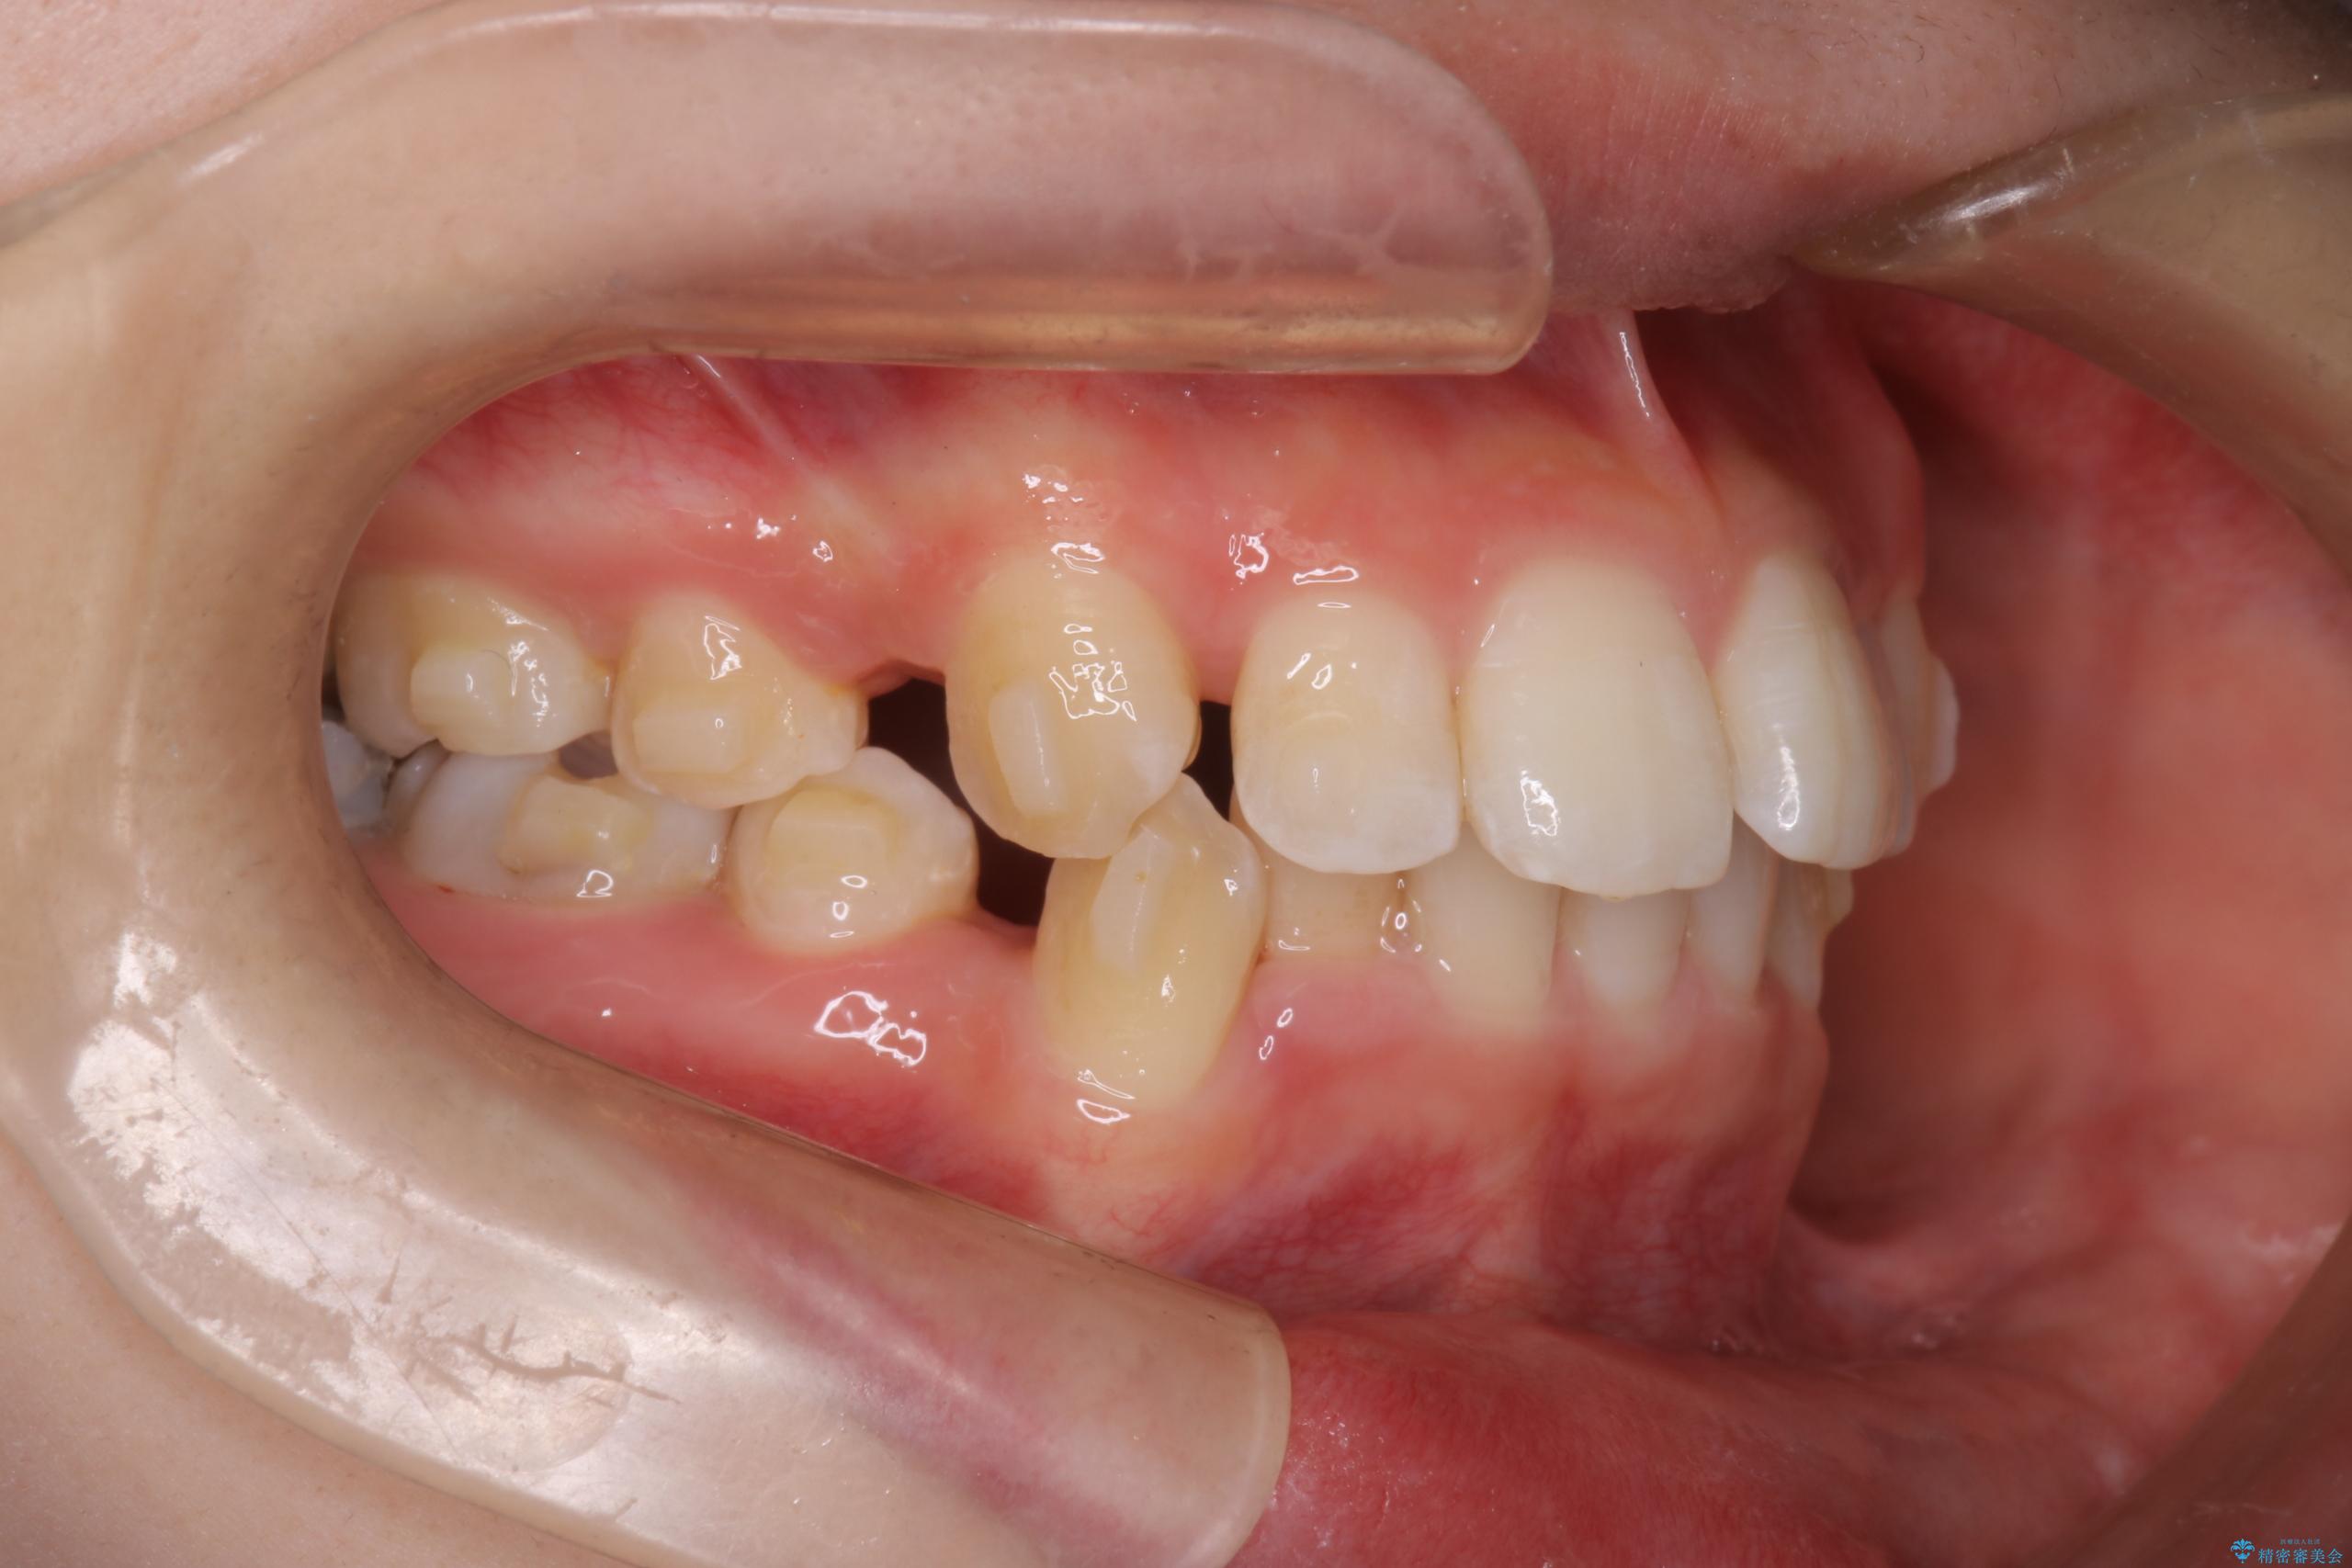

- 前歯から奥歯にかけて歯の重なりが激しい歯のがたつき(重度叢生)を主訴にご来院されました。精密検査の結果、歯が並ぶスペースが大幅に不足しており、歯並びを整え、口元を美しく引っ込めるためには、スペースの確保が必要と診断しました。そこで、上下左右の第一小臼歯(4番目の歯)を計4本抜歯し、そのスペースを利用して歯並び全体を整える抜歯矯正の治療計画を立案。装置には、透明で目立たないインビザラインを採用し、審美性と治療効果の両立を目指しました。

今回の治療では、重度の叢生を改善するため、まず計画通り上下左右4本の小臼歯を抜歯し、歯を並べるための十分なスペースを確保しました。装置には透明で取り外し可能なインビザラインを使用。抜歯によってできたスペースを最大限に活用し、マウスピースを定期的に交換しながら、デコボコを解消しつつ、前歯を効果的に後退させました。

治療の結果、長年の悩みであった重度の歯のがたつきが解消され、口元の突出感も改善。機能的にも安定し、審美的にも美しい、理想的な歯並びを獲得していただけました。